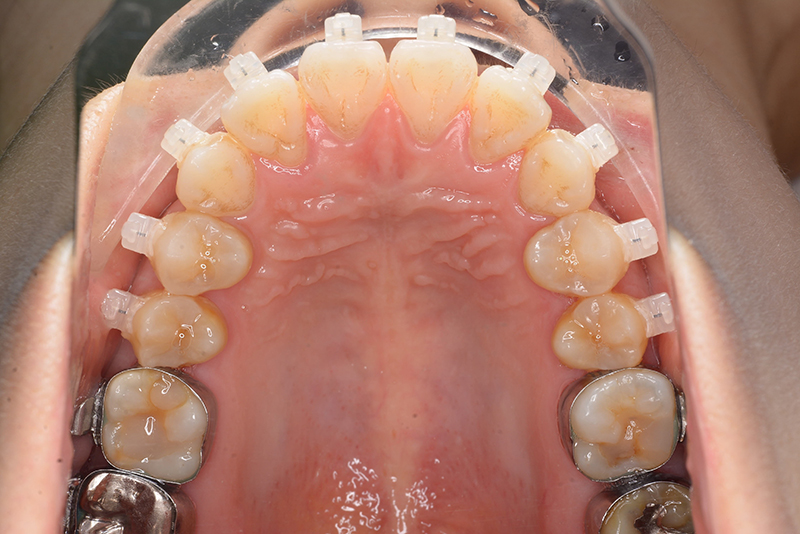

初診時

FP・IOP

口腔内所見 over jet 4.0mm、over bite 2.0mm、臼歯関係Ⅰ級、犬歯関係Ⅱ級で上顎前歯は唇側傾斜を呈しており、上下顎前突の様相を呈していた。